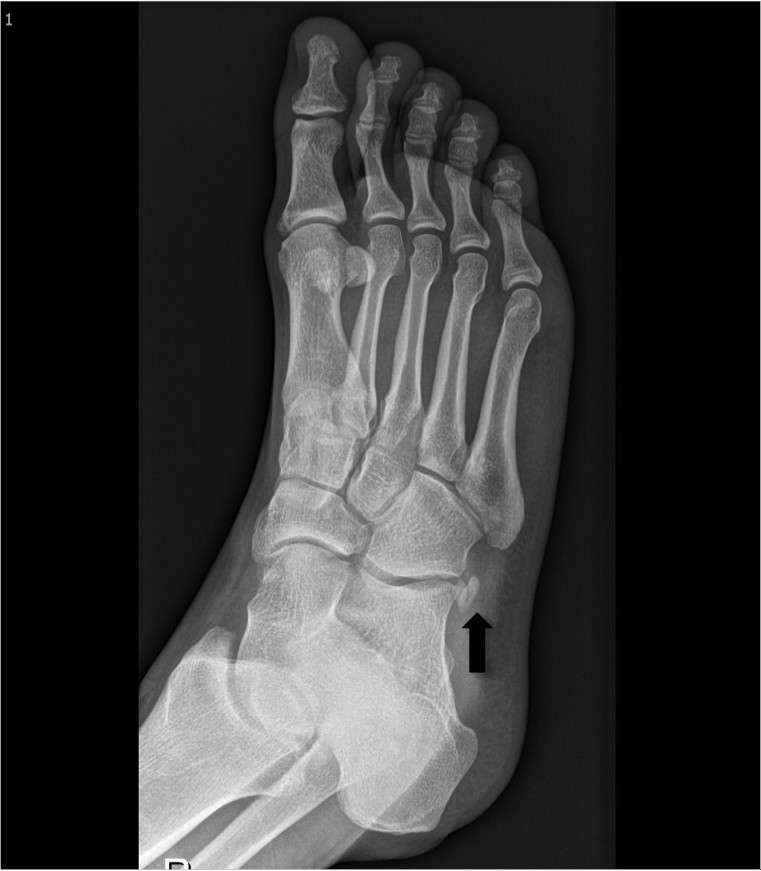

跖间骨(图5)是一种相对不常见的足部辅助骨,通常位于第一和第二跖骨基部之间,通常是双侧的。发病率介于1.2和14%之间。其病因尚不确定:可能是由于跗骨骨间质形成时的变化,或者它可能是真正的骨化辅助中心。

大多数跖间骨无症状,出现症状的患者会抱怨疼痛和感觉异常,从足背到拇趾和第二趾的麻木,随着跖屈而增加,这些症状也被称为前跗管综合征,其由下部支持带压迫深腓神经引起。CT或的足标准前后位、侧位和斜位X线片以识别跖间骨并确定某些体征,例如疼痛的位置,形状和大小。

49afd133e444913fa49772baff7da524.jpg

图5:一名男子右脚的前后位X线片,在第一跖间间隙的右脚中部背部有压痛,显示有一个跖间骨(黑色箭头)。